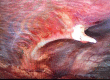

Non-traumatic complications of a solitary rib osteochondroma; an unusual cause of hemoptysis and pneumothorax

Osteochondromas are a very common and usually asymptomatic entity which may originate anywhere in the appendicular and axial skeleton. However, the ribs are a rare site of origin and here they may prove symptomatic for mechanical reasons. In this case report, we describe an unusual case of a symptomatic osteochondroma of the rib secondary to its location and unique shape, ultimately requiring surgical intervention.